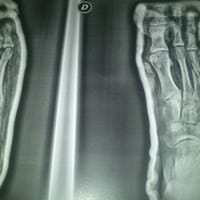

Fractura primer meta y 2 meta pie derecho con fisura en el 3 meta

Http://subefotos.com/ver/?a9ca692e8a8d4499656cd7b3748c96aeo.jpg http://subefotos.com/ver/?77d4f6c00dacafb2e02b900c7def2d0ao.jpg http://subefotos.com/ver/?2c2c47fc22a53a5b53a5358faef75a1ao.jpg Hola buenas, arriba adjunto las radiografias a ver que...

Fractura 3 meta pie derecho

Pues me gustaría saber que pinta le ven, me han comentado algunos fisios que tendré que pasar por quirófano, saludos y gracias de antemano.

Fractura del 3º Metatarsiano pie dcho

Hace 1 mes me partí el 3 metatarsiano en un partido de liga, fue en un balón dividido y creo que me dio un punterazo. En ese mismo momento pido el cambio y me trasladan a urgencias, donde me diagnostican la fractura y me colocan una escayola, solo...